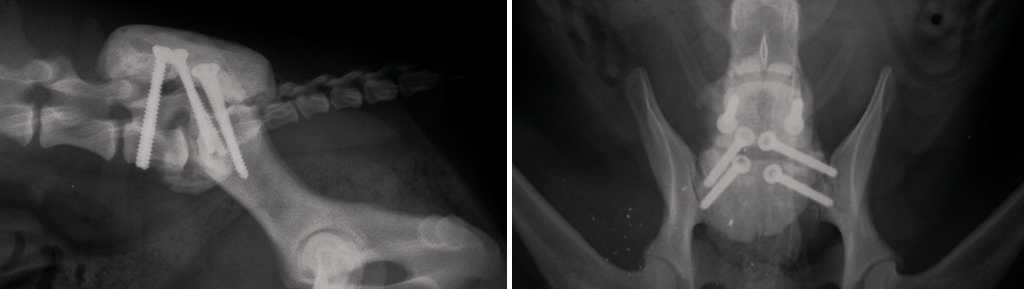

Дорсальная декомпрессия + дистракция + стабилизация с использованием костного цемента и имплантов (ортопедические винты и спицы)

Суть операции заключается в проведении декомпрессии, как описано выше, далее выполняют дистракцию L7–S1, затем устанавливают винты и/или спицы в межпозвоночные суставы, после чего проводят транспедикулярное введение винтов и/или спиц в L7 и S1 (допускается проведение имплантов из крестца в подвздошную кость). В заключение вся конструкция покрывается костным цементом. Данная техника операции используется в основном у пациентов с небольшой массой тела – до 20–25 кг. Основные проблемы, возникающие у собак весом более 25 кг, которым была выполнена операция по методике «костный цемент + дистракция + винты и/или спицы», это перелом конструкции (цемент/винты/спицы), расшатывание и миграция имплантов. Как следствие – реоперация (рис. 7 ,7а).

Рис. 7. Этапы операции DLSS – введение имплантов и нанесение костного цемента. А – введение винтов в L7–S1, В – укладка жирового трансплантанта на место ламинэктомии,С – нанесение костного цемента для фиксации имплантов.

Рис. 7а. Послеоперационный рентген.